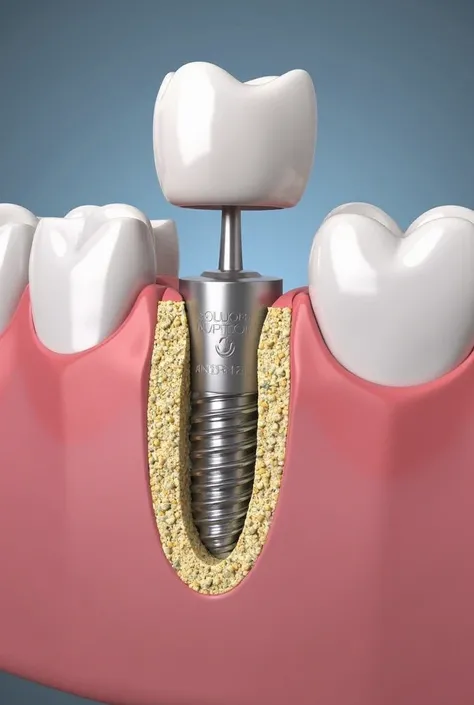

Create an artistic image that reimagines a dental implant as a luxurious work of art. The implant should be central in the composition, with intricate details that highlight its structure, such as the titanium post and the crown, all rendered in a refined and elegant manner. Surround the implant with artistic elements like flowing gold accents, delicate textures, and subtle patterns that evoke a sense of luxury and precision. The background can be minimalist, using soft gradients or abstract forms to keep the focus on the implant while enhancing the overall aesthetic. The image should blend the technical precision of a dental implant with the elegance and sophistication of fine art, creating a piece that is both visually striking and conceptually unique

Create an artistic image that reimagines a dental implant as a luxurious work of art

such as the titanium post and the crown